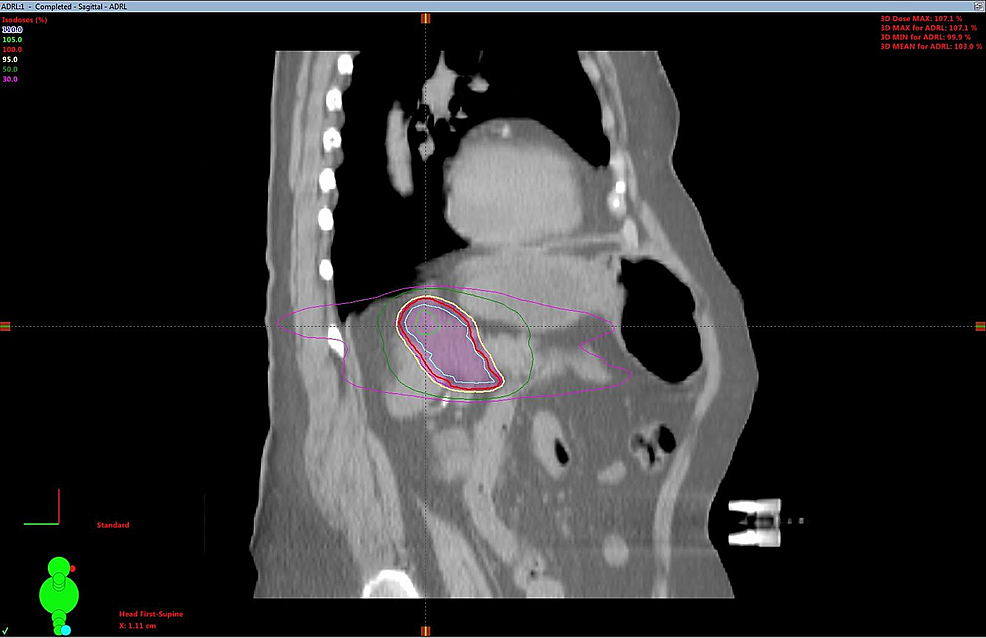

SBRT treatment planning CT scans can be seen in Figures 2-5. The left adrenal mass was treated first in June 2012 followed by the right lung mass one month later. 4D CT simulation with abdominal compression was performed for each site. Cone-beam CT image guidance was used prior to each fraction.

A dose of 30 Gy over six fractions was delivered via linear accelerator to the left adrenal mass utilizing a five-field intensity-modulated radiation therapy (IMRT) technique with six MV photons, to a prescribed isodose of 100%. The right lung mass was treated with a nine-field non-coplanar SBRT technique with a dose of 48 Gy in four fractions over two weeks, prescribed to the 80% isodoses. Treatment concluded in August 2012. Treatment was well tolerated, with a short bout of nausea reported.